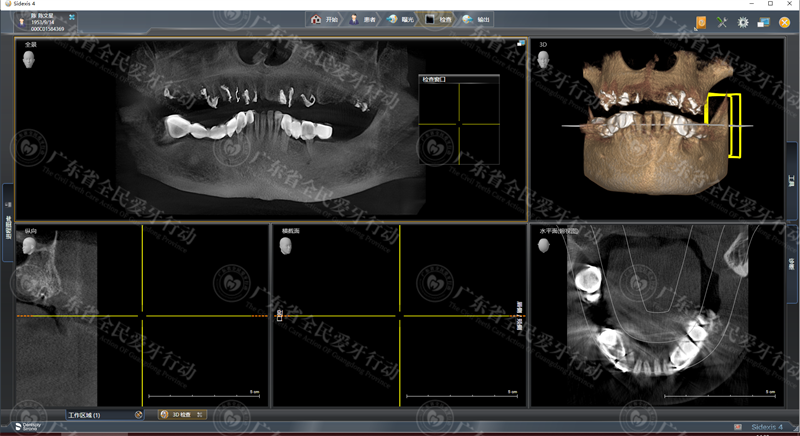

术前CT:上颌牙缺失严重,多残根烂牙

术前CT:上颌种植6颗种植牙,恢复上半口牙

经过详细的数字化拍片检查,专家为陈伯制定了一套既能减少种牙时间,又能更快恢复半口好牙的方案——利用全智能精控种植“all-on-6”上面植入6颗种植体,恢复稳固半口上颌好牙。